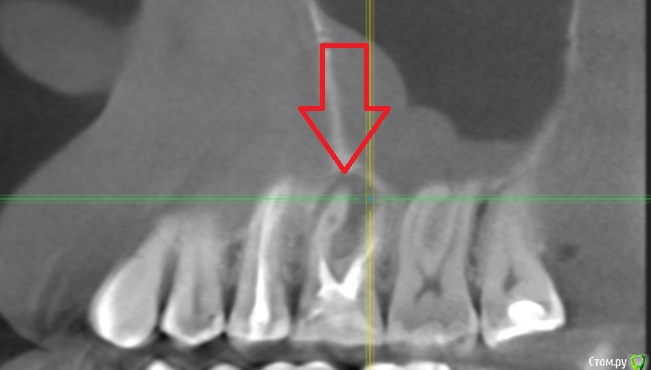

twodudu Опубликовано 12 декабря, 2019 Поделиться Опубликовано 12 декабря, 2019 (изменено) стоит проблема- удалить, чтобы не беспокоил .Или же лечить. Что скажите? зуб номер 6, находится вверху справа. На корне киста Изменено 12 декабря, 2019 пользователем twodudu Ссылка на комментарий

DmitrySH Опубликовано 12 декабря, 2019 Поделиться Опубликовано 12 декабря, 2019 (изменено) каков шанс на выздоровление? т.к у врачей есть мнение, что канал не удастся "пройти", и корень так же может портиться снаружи по стенкамЛучше лечить под контролем микроскопа, корень достаточно тонкий. не удастся пройти, тогда удалять. Если все нормально обработать, то шанс на выздоровления достаточно хороший Изменено 12 декабря, 2019 пользователем DmitrySH Ссылка на комментарий

twodudu Опубликовано 12 декабря, 2019 Автор Поделиться Опубликовано 12 декабря, 2019 Надежность этого зуба будет понятна после удаления пломбы и ревизии каналов с очагом воспаления. Сам по себе очаг воспаления не является чем-то неизлечимым. Больше вопрос в состоянии твердых тканей зуба. Если при ревизии каналов не будет выявлено каких-то критичных моментов, то зуб вполне надежный. зуб лечен (повторно) , около 11 месяцев назад. Один канал оказался не пройден . Доктор его не смогла найти, говорит, что если изначально он не был найден и отремонтирован, то и при повторном вскрытии не найти. Есть вероятность, что он вообще расколется. Одна надежда на микроскоп, но вот у специалистов все расписано на пару недель вперед.А зуб ужасно болит и десна/щека опухла. Сегодня хирург наложил дренаж Ссылка на комментарий